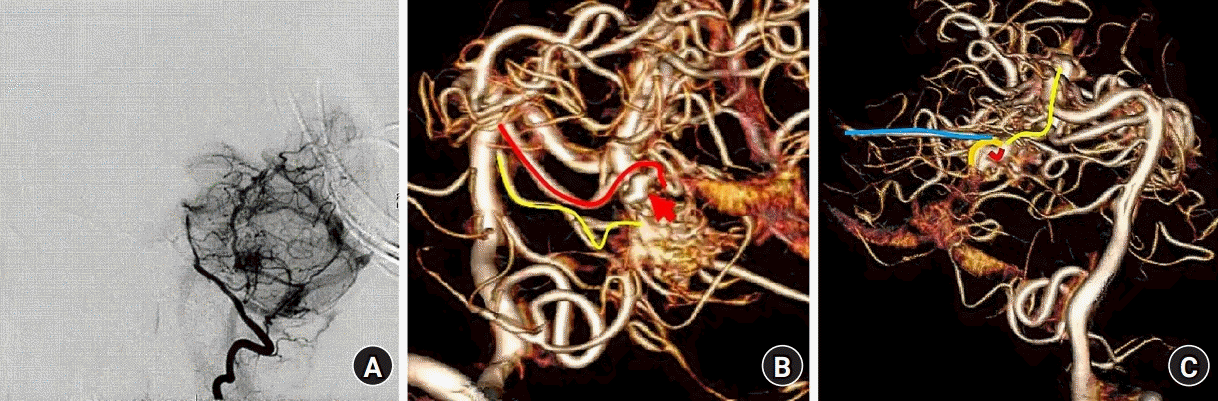

After admission, the digital signature algorithm (DSA) results revealed the presence of an AVM in the right cerebellar hemisphere (Fig. 1A, Supplementary Fig. 1) involving the right superior cerebellar pontine artery and perforating branch artery as well as flow-related aneurysms in the superior cerebellar artery (Fig. 1B). Neither the bilateral internal carotid artery nor external carotid artery were involved in blood supply. The AVM drainage vein comprised a short main drainage vein and three secondary drainage veins (Fig. 1C, Supplementary Fig. 2). The treatment team determined that the first stage would involve treatment of the aneurysms, while the second stage would involve cerebral AVM treatment using a transvenous approach.

Fig. 1.

(A) Right cerebral angiography. (B) The red line is the right superior cerebellar artery, the yellow line is the perforating branch of the pontine, and the red arrow is a flow-associated aneurysm of the superior cerebellar artery. (C) The red line is the main drainage vein, and the orange, yellow and blue lines are the secondary drainage veins.